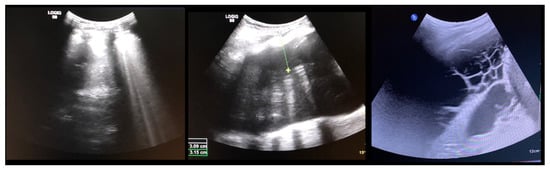

| 1 | 13.3 | F | 2 | T5-T12 right T12-L4 left | Pleural effusion | 2 weeks | Right | Minor dyspnea | Ultrasound, conservative treatment |

| 2 | 17.6 | F | 4 | T6-L1 right | Pleural effusion | 2 weeks | Right | Dyspnea, fatigue | 2 × aspiration |

| 5 | 16.2 | F | 2 | T5-T11 right T11-L3 left | Pleural effusion | 3 weeks | Bilateral | Chest pain and elevated CRP levels | Bilateral aspiration, forced diuresis and i.v. albumin treatment |

| 8 | 17.9 | F | 1 | T10-L3 left | Pleural effusion | 4 days | Left | None, effusion diagnosed on routine post-op X-ray | Aspiration followed by chest tube reinsertion for recurrent effusion |

| 9 | 14.6 | F | 2 | T5-T11 right T11-L4 left | Pleural effusion | 3 weeks | Right | Fatigue, dyspnea | Chest tube reinsertion, antibiotics for co-existing pyelonephritis |

| 14 | 16.3 | F | 2 | T5-T11 right T11-L4 left | Pleural effusion | 5 weeks | Right | Dyspnea | Aspiration |